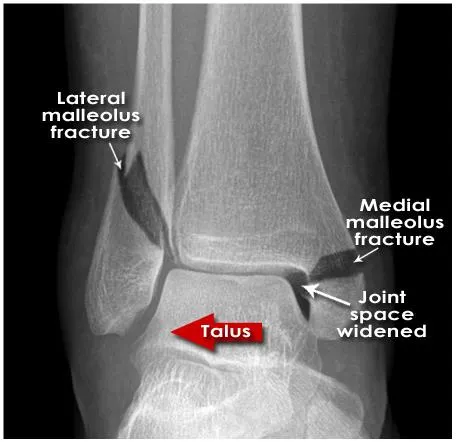

Medial mortise wide

Suggests instability

Lateral displacement of talus (weber B)

Medial malleolus fx.